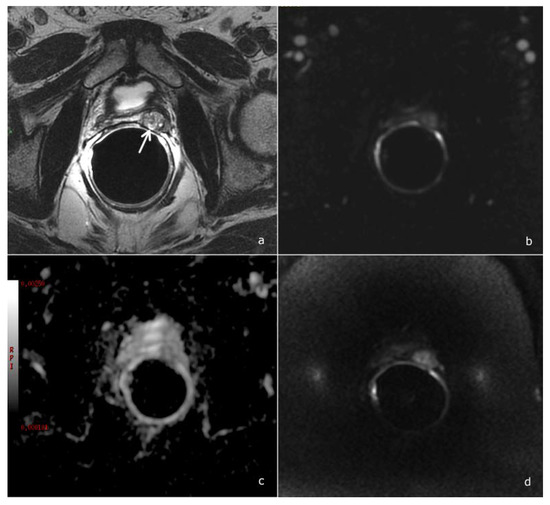

2.2. mpMRI Protocol Study

- Morphological study: Fast Relaxation Fast Spin Echo T2-weighted (T2w) sequences in the sagittal, axial and coronal planes, covering the prostate lodge.

- Diffusion-weighted imaging (DWI): a single-shot echo-planar sequence with a high b-value (2000 s/mm2) and another single-shot echo-planar sequence with two different b-values (50 and 1000 s/mm2), this latter for the calculation of the apparent diffusion coefficient (ADC) map.

- DCE acquisition: three-dimensional (3D) T1-weighted Time-of-Flight Spoiled Gradient-Recalled sequence on the axial plane during the intravenous injection of a gadolinium-based contrast agent at a flow rate of 3 mL/sec followed by 15 mL of saline solution. The 3D data sets were acquired with a 10 s temporal resolution; the acquisitions before the contrast agent administration were analyzed to detect foci of hemorrhage.

2.3. Image Analysis

- Scores of 1 and 2 were assigned to lesions with a very low and low likelihood of recurrence

- Score 3 was assigned if the presence of recurrence was uncertain

- Scores 4 and 5 were assigned when the likelihood of recurrence was high and very high